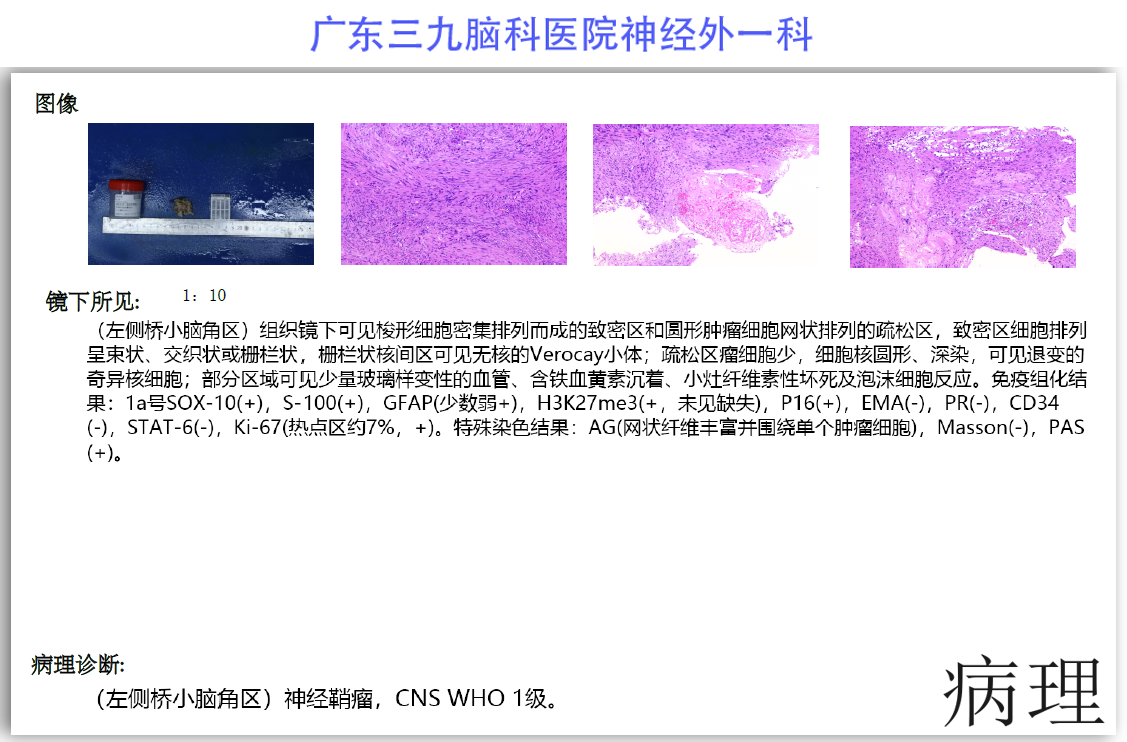

陈某某,女,41岁,因“左侧面部麻木3月余,吞咽困难半月余”于2024-02-17入院。患者3个月前出现左侧面部麻木,偶尔伴有头晕和左侧流泪,但没有听力下降或耳鸣。同时,患者也出现肢体乏力和行走不稳,但未接受任何治疗。半个月前,患者发现吞咽硬质食物稍有困难,同时左侧面部麻木加重。因此,前往当地医院就诊,并进行头颅MR检查,结果显示左侧CPA区存在占位性病变。为了进一步治疗,患者转诊至我院就医。术前检查显示:左侧角膜反射减弱,左侧鼻唇沟略微变浅,伸舌稍微右偏,咽反射迟钝。门诊诊断为“左侧巨大听神经瘤”,收治至我科进行住院治疗。手术过程顺利,术后患者恢复良好,面部轻度瘫痪与术前相同。术后病理检查结果确认为听神经瘤。